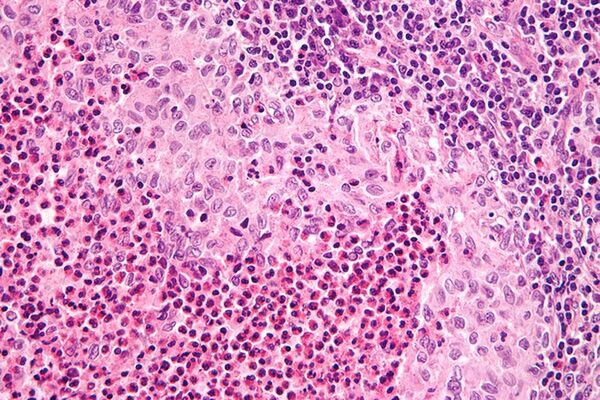

Langerhans Cell Histiocytosis (LCH)

Langerhans cell histiocytosis is a type of cancer that can damage tissue or cause lesions to form in one or more places in the body.